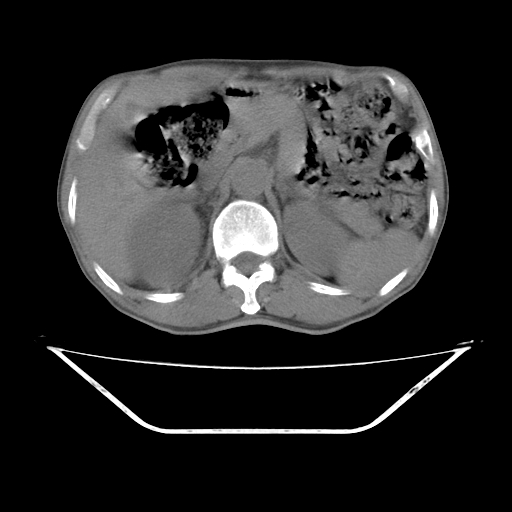

平扫

考虑右肾盂癌,肾动脉受侵,右肾功能减退,右肾盂输尿管积水,管壁增厚,考虑种植转移,应该把下面扫完的

考虑右侧肾盂癌。右侧输尿管扩张未扫描完。

右肾盂癌,肾动脉受侵,右肾盂输尿管积水,管壁增厚,考虑种植转移

右肾盂移行细胞癌并右输尿管中段转移.肾积水.

1.右侧肾盂癌伴肾盂积水。

3.右侧上段输尿管扩张,原因:(1)积水所致;(2)种植。